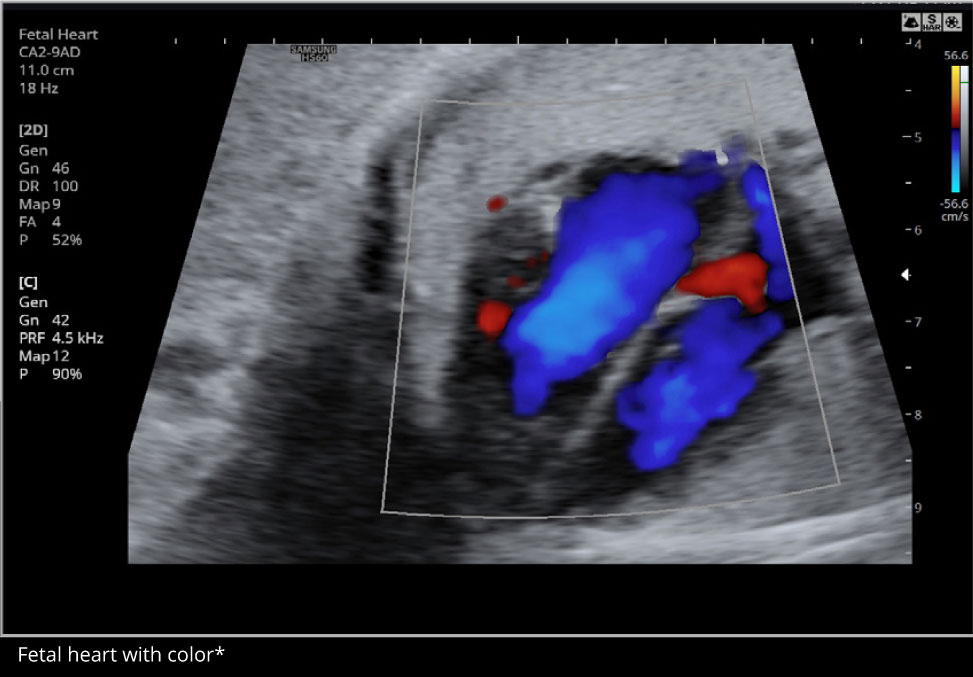

5D Heart Colorâ„¢

5D Heart Colorâ„¢ allows evaluation of fetal cardiac structures for potential blood flow disturbances, an important component of fetal cardiac examination. Using STIC volume datasets, color Doppler sonography is demonstrated in standard fetal echocardiography views in a single display.